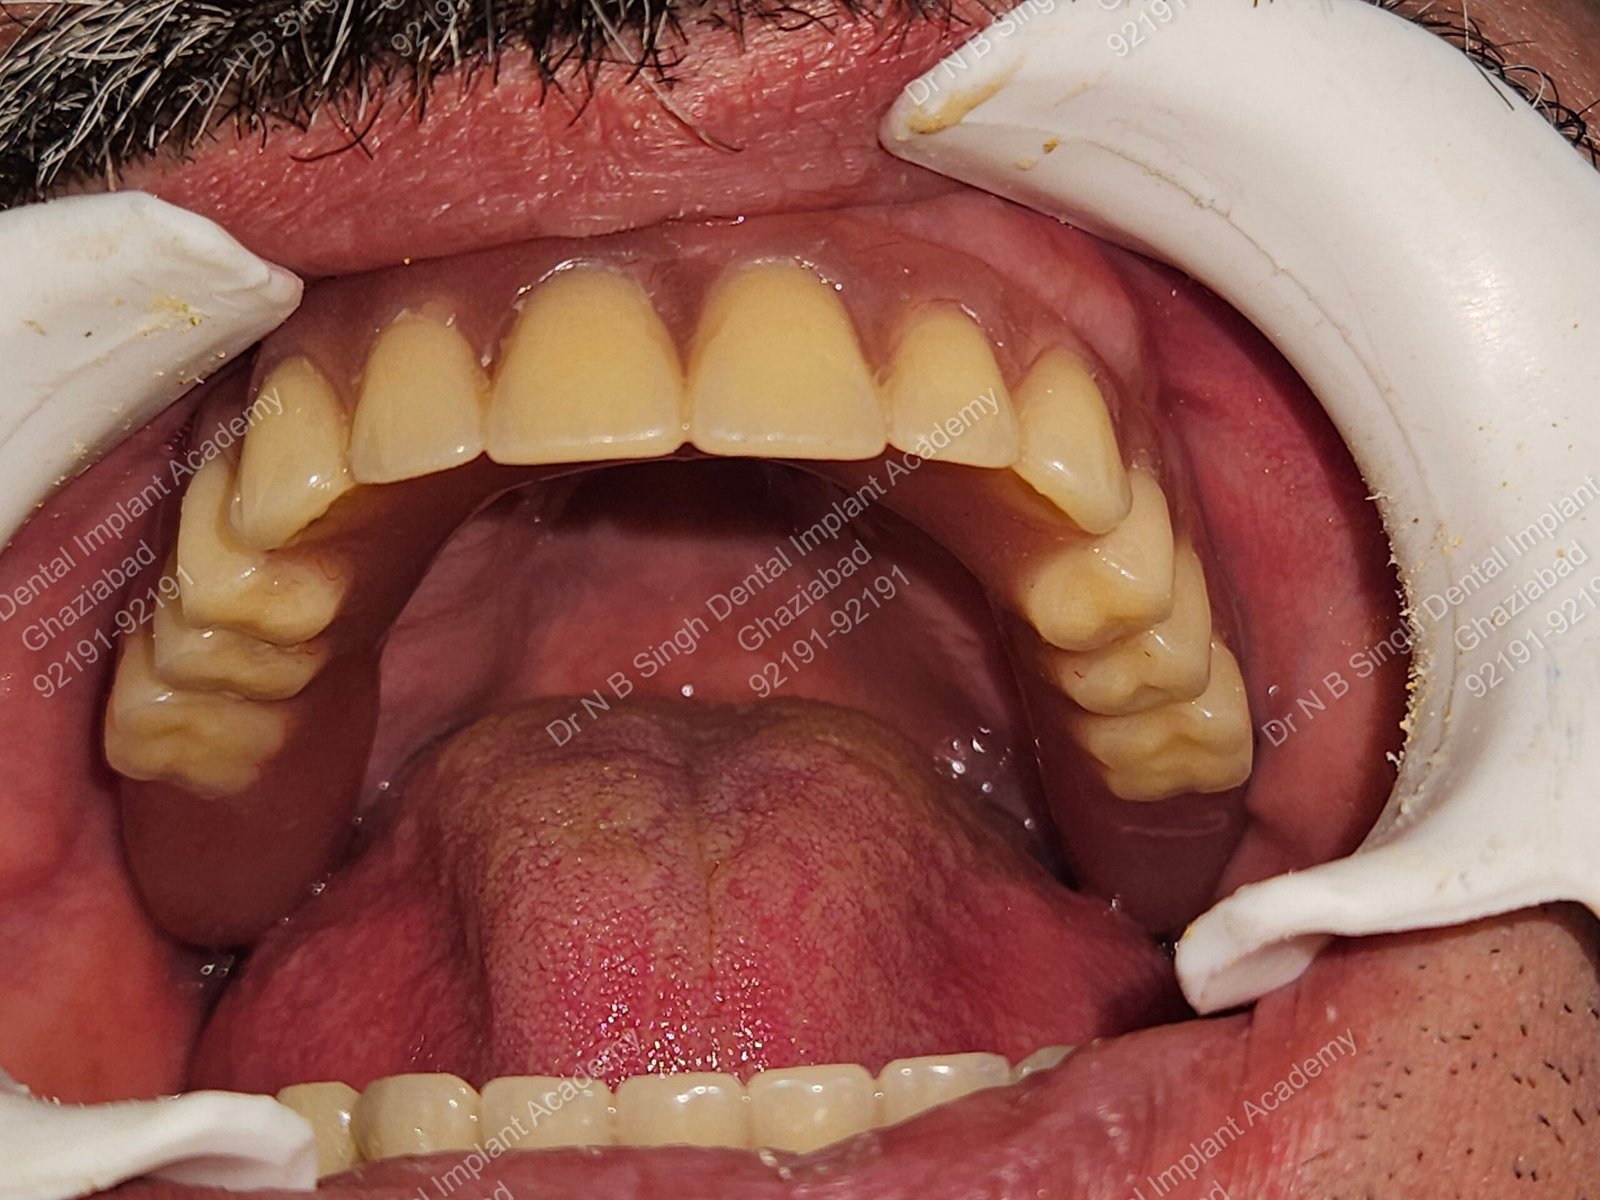

1006 Basal implant full mouth-DEEPAK

1006 -29

1006 -28